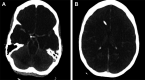

Figure 1.

Non-contrast CT head demonstrating increased attenuation in cortical sulci and within the major cisterns mimicking the appearance of diffuse subarachnoid hemorrhage. The underlying parenchyma is seen to be diffusely edematous and hypoattenuated due to global hypoxic-ischemic injury.